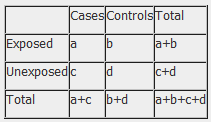

3. Analysis of case-control studies

The odds ratio (OR) is used in case-control studies to estimate the strength of the association between exposure and outcome. Note that it is not possible to estimate the incidence of disease from a case control study unless the study is population based and all cases in a defined population are obtained.

The results of a case-control study can be presented in a 2x2 table as follow:

The odds ratio is a measure of the odds of disease in the exposed compared to the odds of disease in the unexposed (controls) and is calculated as:

Example: Calculation of the OR from a hypothetical case-control study of smoking and cancer of the pancreas among 100 cases and 400 controls. Table 1. Hypothetical case-control study of smoking and cancer of the pancreas.

OR = 60 x 300 100 x 40 OR = 4.5 The OR calculated from the hypothetical data in table 1 estimates that smokers are 4.5 times more likely to develop cancer of the pancreas than non-smokers. NB: The odds ratio of smoking and cancer of the pancreas has been performed without adjusting for potential confounders. Further analysis of the data would involve stratifying by levels of potential confounders such as age. The 2x2 table can then be extended to allow for stratum specific rates of the confounding variable(s) to be calculated and, where appropriate, an overall summary measure, adjusted for the effects of confounding, and a statistical test of significance can also be calculated. In addition, confidence intervals for the odds ratio would also be presented.